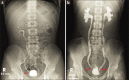

Figure 2

Typical intravenous urography findings in a patient with (a) mild ketamine cystitis with contracted bladder and ureteral stricture (arrow), and (b) severe ketamine cystitis and bilateral obstructive uropathy (arrows)